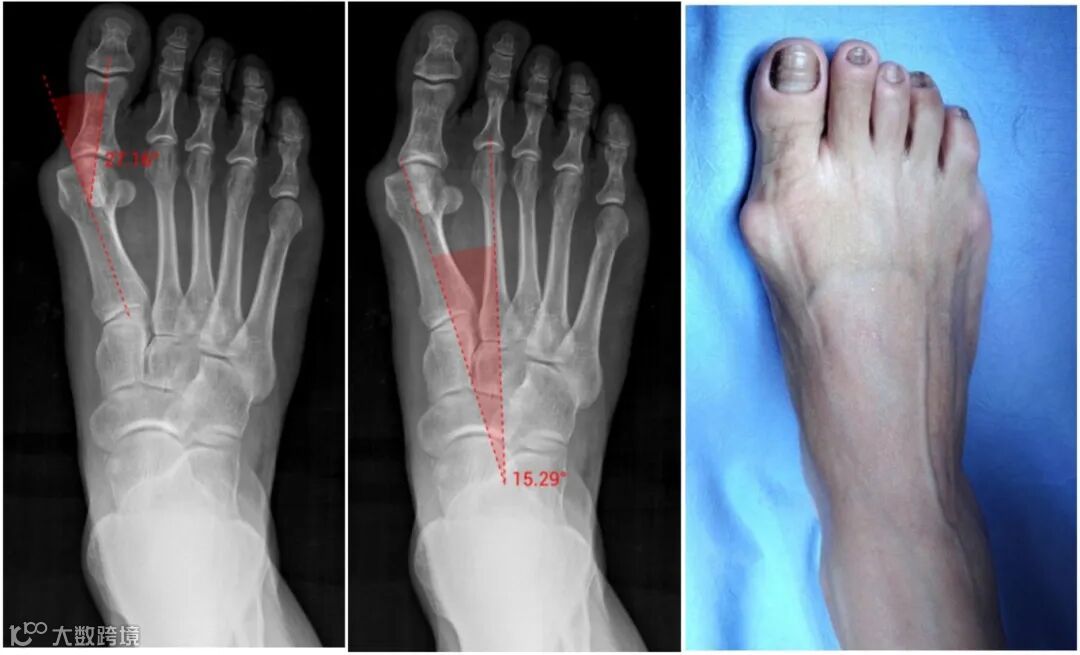

女,45岁,右足中度拇外翻。第一跖趾角: 27.16°,跖骨间角:15.29°。